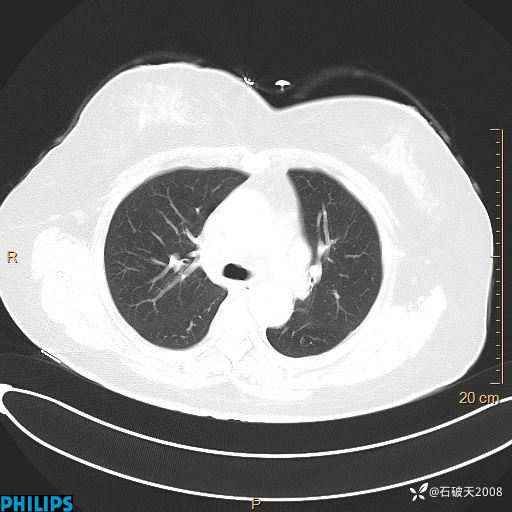

肺结节病?纵膈型肺癌?淋巴瘤?有点意思,欢迎围观

女 52岁 主 诉:咳嗽10余天,咳痰2天。

现病史:10余天前无明显诱因出现咳嗽,呈阵发性干咳,伴咽喉部发痒,无咽痛,无咳痰,无鼻塞、流涕、打喷嚏,无发热、畏寒、寒颤,无头痛、头晕,无胸闷、胸痛,无反酸、烧心,无腹痛、腹泻,无尿频、尿急,无皮疹等,在当地诊所求治,给予口服药物治疗(具体不详),病情无好转。遂在当地社区卫生服务中心开具口服药物治疗(具体不详),疗效欠佳。2天前出现咳痰,在我院门诊求治,行胸部CT提示肺部感染,建议住院,患者要求口服药物治疗,目前仍咳嗽、咳白色粘痰,白天量多,夜间自觉喉部喘鸣音,遂再次来院就诊,以“肺部感染”为诊断收入院。发病以来,神志清,精神可,饮食可,夜间睡眠差,大小便正常,近期体重无明显变化。

肺窗